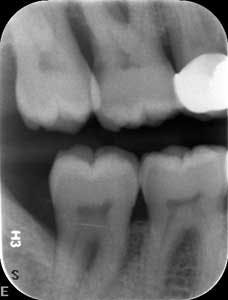

Dental examination revealed gingival swelling and bleeding on probing. Periodontal probing showed moderate-to-deep pocket depths in all posterior teeth (figures 1–3). Generalized bone loss was observed on radiographs (figures 4–6). Tooth vitality and percussion tests were negative. Teeth 2, 3, 31, 14, and 15 had Class III mobility. The patient was diagnosed with Type IV chronic adult periodontitis. Treatment options were discussed, and, after explanation, the patient agreed to the LANAP procedure.

At nine months, the patient’s tissues appeared pink with no inflammation. Radiographs revealed new bone growth, especially around teeth Nos. 3, 15, and 31 (figures 10–12). The patient reported his HbA1c level stable at 8.2.

Patient presentation before LANAP treatment (figures 1–6)

Radiographs nine months after LANAP treatment (figures 10–12)